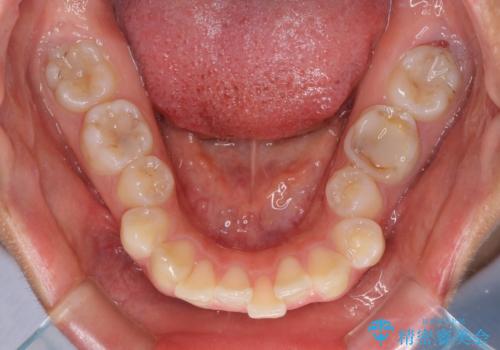

- 咬み合わせと口元の突出感を気にして来院された患者様です。

上顎に対して、下顎が後方にある咬み合わせであるため、上顎左右小臼歯のみの抜歯か、下顎左右小臼歯も抜歯とするのか悩むところでした。

まずは上顎のみ抜歯を行って矯正治療を進め、下顎小臼歯も抜歯が必要となれば速やかに抜歯することとしました。